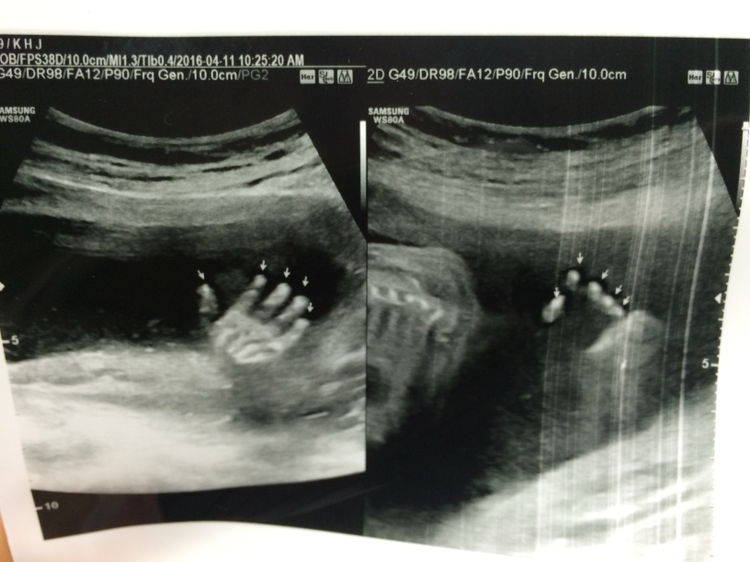

내 배에 올려진 초음파 기계. 그 기계가 움직이는 방향에 따라 아이의 작은 얼굴과 작은 손가락, 발가락, 심장 하나까지도 자세히 볼 수 있었다. 내 배속에 저렇게 작은 아이가 자라고 있다니.... 신기함과 신비로움이 공존하는 미묘한 감정이 내 안에 흐르고 있었다.

매번 검사하러 갈 때마다 많이 커 있는 아이. 선생님께서는 아기가 태동도 잘하고 있다고 칭찬을 해주셨다. 다만 19주부터 먹기 시작한 커피 때문인지 아니면 물을 너무 적게 먹어서인지 선생님께서는 양수가 조금 적다고 아이를 위해 물을 많이 먹어줘라고 하셨다. (당분간 커피는 끊는 걸로) 그리고 아이는 또 한 번 반전 없이 아들임을 입증했다. 또 다리를 벌리고 ‘엄마 난 아들이에요’를 아낌없이 보여주었다. 이제 조금씩 사람의 형태를 갖추어져 가고 있는 아이. 아이가 클수록 엄마가 된다는 설렘도 커져가는 것 같다. 19주 뒤엔 진짜 어떤 모습으로 태어날지 그 모습이 정말 궁금해진다.

결과는 자궁근종 때문이라는 결론이 나왔다. 2센티밖에 안 되는 작은 근종인데도 불구하고 아팠던 이유는 근종의 위치도 애매하고 아이가 태동을 하면서 그걸 건드려서 그렇다고 하셨다. 그래도 다행히 태아에 문제가 있는 건 아니라고 하셔서 아팠지만 난 안도의 한숨을 내 쉴 수 있었다. 그리고 아이도 잘 크고 있다고 하셨고 혹시나 해서 자궁경부 길이도 재어봤는데 다 괜찮다고 하셨다. 참고로 이맘때 나처럼 이렇게 자궁근종으로 인한 통증을 호소하며 오는 임산부들이 많다고 한다. 하지만 자궁근종이 크든 작든 임신한 상태에선 치료할 수 있는 방법이 없기 때문에 엄마는 아파도 견딜 수밖에 없다고.... 그래서 난 진통제만 처방받고 집으로 돌아갔다. 진통제를 먹었는데도 통증은 여전. 계속 흐르는 눈물. 이제 4개월이나 남았는데 이 자궁근종 통증을 출산 때까지 기다려야 하나 온통 걱정뿐이었다. 이렇게 아프니 먹는 것도 싫어지고 그저 따뜻한 죽만 생각났다. 엄마라도 있었다면 아빠라도 있었다면 이렇게 내가 아플 때 죽이라도 해주었을까..? 하는 생각에 괜스레 더 우울해지는 마음.